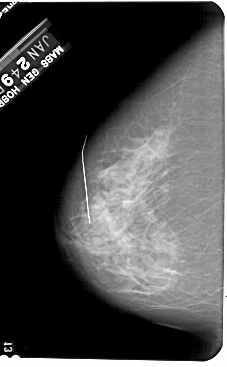

A_1236_1.RIGHT_MLO

LEFT_CC LINES 5491 PIXELS_PER_LINE 3391 BITS_PER_PIXEL 12 RESOLUTION 43.5 NON_OVERLAY

FILE: A_1236_1.RIGHT_CC.OVERLAY

TOTAL_ABNORMALITIES 1

ABNORMALITY 1

LESION_TYPE CALCIFICATION TYPE PLEOMORPHIC DISTRIBUTION CLUSTERED

LESION_TYPE MASS SHAPE IRREGULAR MARGINS SPICULATED

ASSESSMENT 5

SUBTLETY 5

PATHOLOGY MALIGNANT

TOTAL_OUTLINES 1

BOUNDARY